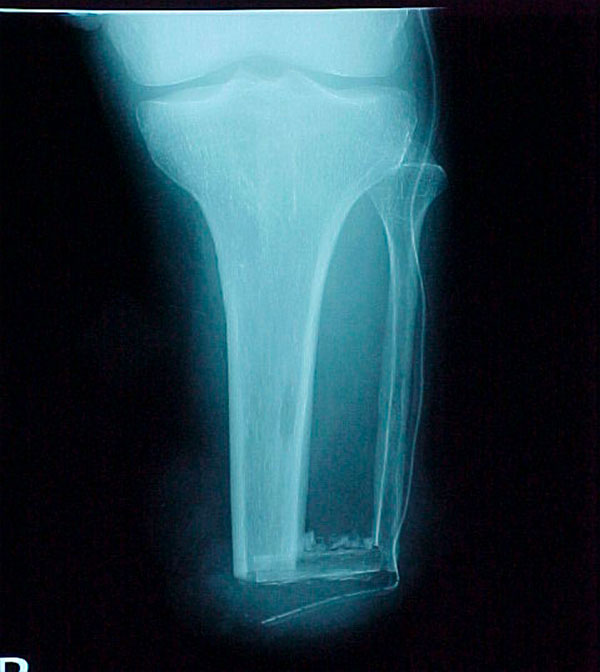

- Primary Objective RCT to evaluate the use of recombinant protein in patients at high risk for nonunion

- Focus Area Reconstructive Surgery & Non-Surgical Management to Improve Bone Healing

- Sponsor DoD OETRP